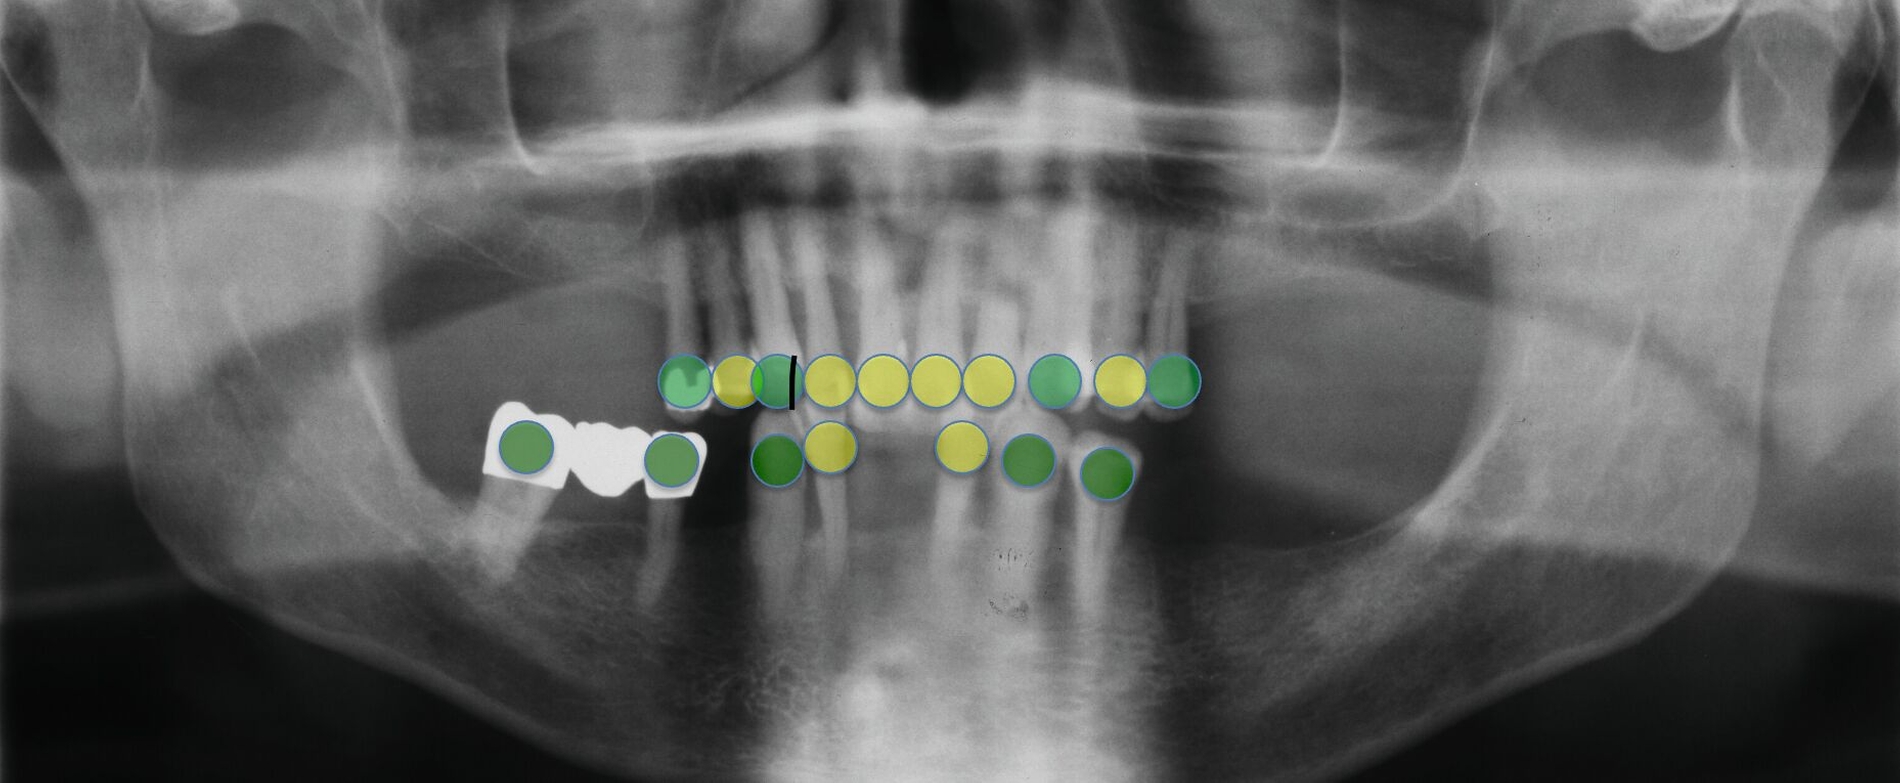

Der Patient wies verkürzte Zahnreihen im Ober- und im Unterkiefer sowie zusätzliche Schaltlücken im Unterkiefer auf (Abbildung 9). Nach Abschluss der ersten beiden Stufen der Therapie (nicht-chirurgische Parodontitistherapie), die darauf abzielte, alle vorhandenen Zähne zu erhalten, wurden an allen Zähnen Sondierungstiefen von maximal vier Millimetern erreicht. Anschließend erfolgte die Planung des definitiven Zahnersatzes im Sinne der aktuellen Leitlinien-Empfehlungen:

Ein Ersatz der Molaren war nicht erforderlich, da der Patient mit der verkürzten Zahnreihe seine Kaufunktion als ausreichend empfand. Aufgrund der erhöhten Beweglichkeit der Oberkieferfrontzähne, die die mundgesundheitsbezogene Lebensqualität stark beeinträchtigte, wurde eine adhäsive Schienung von Zahn 13 bis 21 durchgeführt. Dabei kam ein Polyethylen-Fasernetz (Ribbond, Seattle, USA) zum Einsatz (Abbildung 10). Zur Versorgung der Freiendsituation wurden zwei Implantate mit lokalem Knochenaufbau inseriert und mit implantatverankerten zementierten Einzelkronen versorgt. Die Frontzahnschaltlücke im Unterkiefer wurde mit zwei einflügeligen Adhäsivbrücken aus labial verblendeter 3Y-TZP-Zirkonoxidkeramik (Abbildungen 11 bis 13) geschlossen, die Schaltlücken regio 44 und 46 durch eine Anhängerbrücke, die von Zahn 47 bis Zahn 44 reichte (Abbildung 14).

Danach wurde der Klinikbesuch für den inzwischen 83-Jährigen zu beschwerlich, und er wurde von einem wohnortnahen Zahnarzt betreut. Die von ihm 19 Jahre nach Eingliederung des Zahnersatzes angefertigte Panoramaschichtaufnahme dokumentiert die unveränderte prothetische Versorgung des Unterkiefers sowie die stabile Situation der verkürzten Zahnreihe im Oberkiefer (Abbildung 16). Für eine detaillierte Darstellung des Fallberichts wird auf die Originalpublikation verwiesen [Wolfart und Kern, 2024].